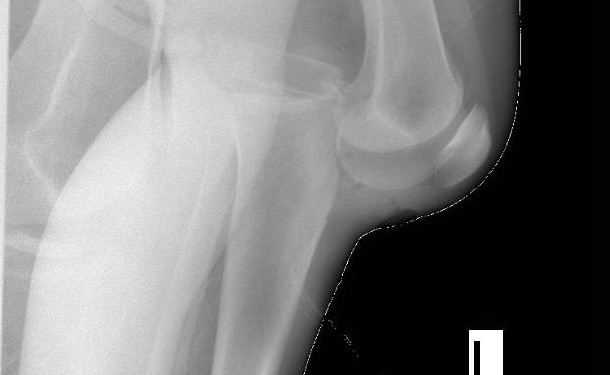

AP lateral oblik diz grafileri

Lateral grafide yağ-sıvı seviyesi (lipohemartrosis) ; intraartiküler kırık